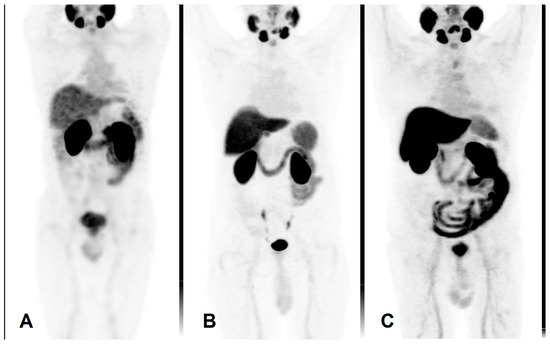

Mean activity of 666 ± 102 MBq [99mTc]Tc-PSMA-I&S (Institute of Isotopes Co., Ltd., Budapest, Hungary) was administered intravenously. Prior to imaging, patients were given oral contrast material (1000 mL of polyethylene glycol solution) to drink continuously, starting 60 min before the examination. Scans were performed on an integrated whole-body SPECT/CT system (Mediso AnyscanTRIO, Mediso Medical Imaging Systems Ltd., Budapest, Hungary). Whole-body SPECT imaging was carried out 6 h after radiopharmaceutical administration, with acquisition parameters set at 360° rotation, 96 projections, 10 s per frame, matrix size 128 × 128, and reconstructed pixel size of 4.22 mm. SPECT data acquisition was supplemented by a low-dose CT scan (120 kV and 70 mA·s). An illustrative image is presented in Figure 5A.

The PET/CT scans were performed using a GE Discovery IQ Gen 2 PET/CT System (GE Healthcare, Chicago, IL, USA). Acquisitions began 90 min post-injection of 3.7 MBq/kg of the intravenous radiopharmaceutical. Prior to imaging, patients were administered a positive iodinated oral contrast agent, which they were instructed to drink continuously starting 60 min before the scan. The PET scan was performed in three-dimensional (3D) mode, with each bed position scanned for 2.5 min. The field of view was 20 cm with a 30% overlap between bed positions. Data acquisition was complemented by a low-dose plain CT scan (120 kV and 70 mAs) for mapping purposes. The reconstructed pixel size was 3.65 mm. Routine whole-body mapping was performed, covering the area from the base of the skull to the upper third of the thigh. These are illustrated in Figure 5B,C.

Figure 5. Maximum intensity projection PET images using different radiopharmaceuticals. (A) [99mTc]Tc-PSMA-I&S, (B) [18F]PSMA-1007, (C) [18F]F-JK-PSMA-7.